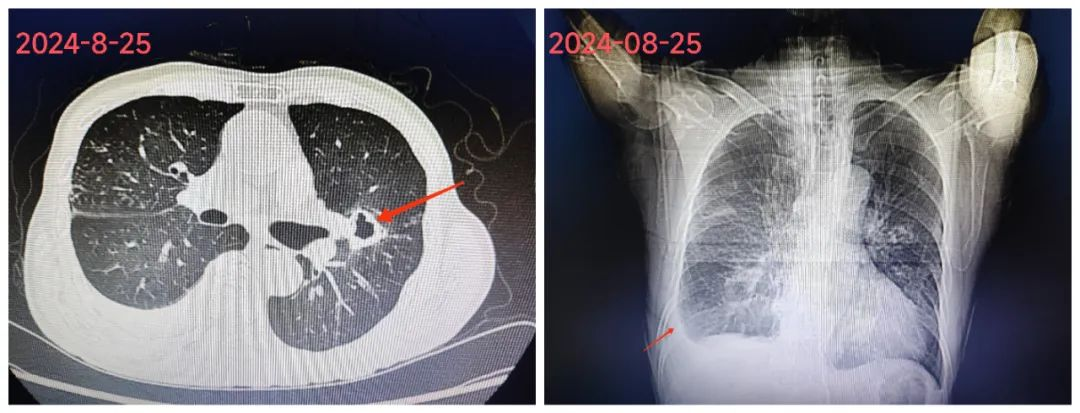

最后,医师团队予加用阿米卡星、克拉霉素、利福平、乙胺丁醇;治疗3天后,患者体温终于恢复正常。经过对病情抽丝剥茧,细致分析,即予以规范治疗,患者病情逐渐好转,复查胸片、胸部CT病灶吸收,目前仍在巩固治疗阶段。

▲8月25日胸部CT

▲9月5日复查胸部CT